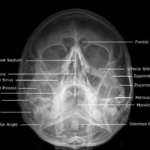

Las radiografías, generalmente llamadas rayos X, producen imágenes como sombras de huesos y ciertos órganos y tejidos. Las radiografías son muy buenas para detectar problemas óseos. Pueden mostrar algunos órganos y tejidos blandos; sin embargo, la MRI y la CT suelen crear mejores imágenes de los mismos. Aun así, las radiografías son rápidas, fáciles de obtener y menos costosas que los otros estudios, por lo que se pueden usar para obtener información rápidamente.

Un tubo especial dentro de la máquina de rayos X emite un haz de radiación controlada. Los tejidos del cuerpo absorben o bloquean la radiación en diferentes grados. Los tejidos densos como los huesos bloquean la mayor parte de la radiación, pero los tejidos blandos, como la grasa o los músculos, bloquean menos radiación. Después de pasar por el cuerpo, el haz alcanza una pieza de un fragmento de película o un detector especial. Los tejidos que bloquean altas cantidades de radiación, como los huesos, aparecen como áreas blancas en un fondo negro. Los tejidos blandos bloquean menos radiación y aparecen en tonos de gris. Los órganos que contienen principalmente aire (como los pulmones) aparecen en negro. Los tumores son por lo general más densos que el tejido que los rodea, por lo que suelen verse en tonos grises más claros.